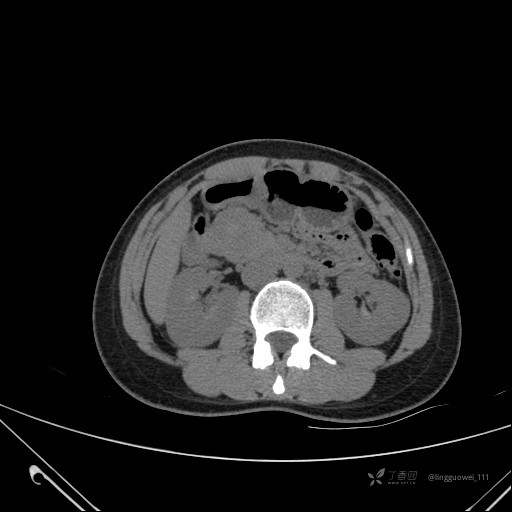

患者性别:女

患者年龄:28岁

主诉:体检发现胰腺病变,行 CT检查。

延迟期:

img